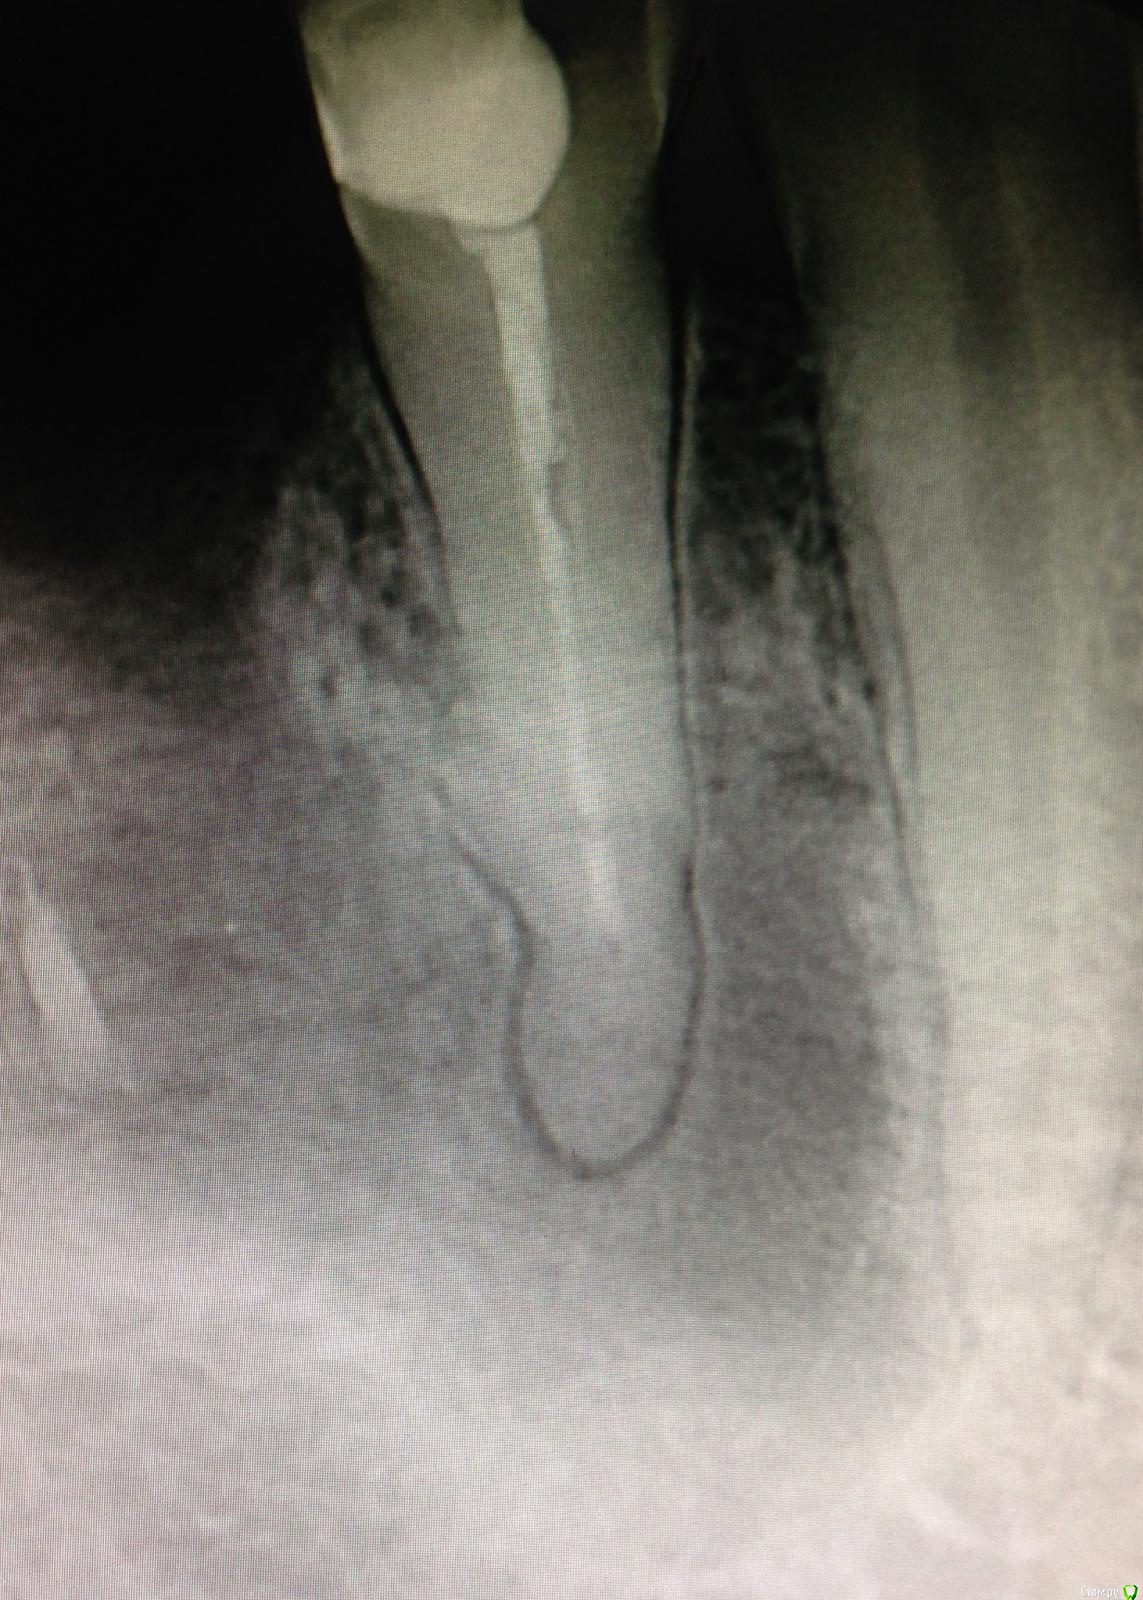

Ico Опубликовано 17 декабря, 2014 Поделиться Опубликовано 17 декабря, 2014 Тут дело не в калибровке. Ведь проблема и в том, что спредеры не лезут до конца(1-2мм не доходя мастер).Они могут просто в стенку упираться,если изгиб у канала имеется,а если изгиб в верхнеи трети как тутhttp://imhocloud.com/images/2014/12/17/2013-08-28-209c390c.th.jpg то латералить можно только маленькими размерами до 25 Ни-Ти. Ссылка на комментарий